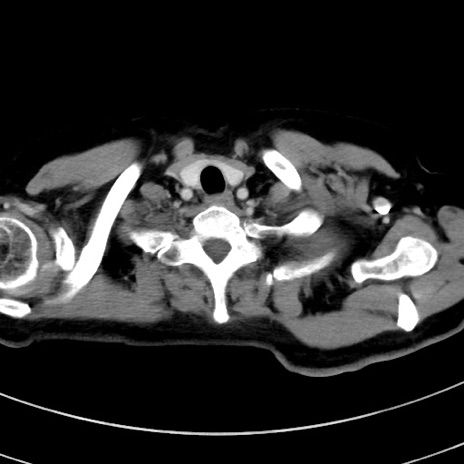

症例9(横断像)

【症例】 60歳代女性

【主訴】むかつき、みぞおちの痛み

【現病歴】3日前よりむかつきがあり、食事がとれない。

【既往歴】糖尿病

【身体所見】発熱なし、心窩部圧痛軽度あるも、腹膜刺激症状なし。

【データ】WBC 7400、CRP 1.92